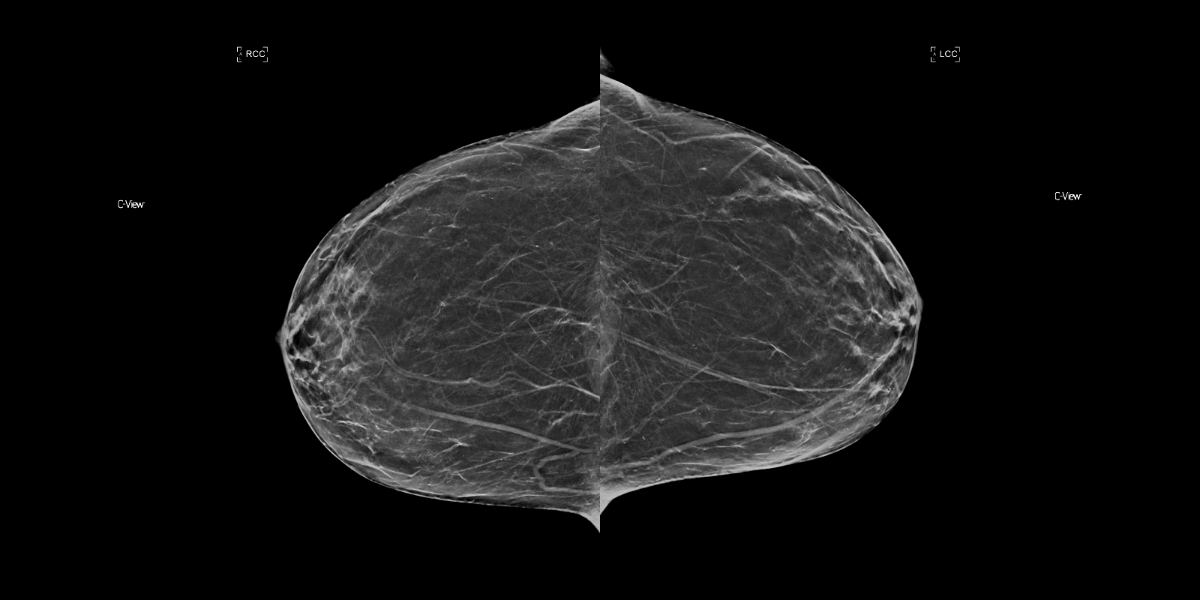

3D Case of the Day (# 4, 2021)

MammoScreen® is utilized to confirm a benign diagnosis.

Clustered microcalcifications in the upper outer quadrant at the junction of the middle and posterior third of the breast were identified on the baseline mammogram by the original reader.

The follow-up examination recommended a stereotactic biopsy of the microcalcifications. Results diagnosed the area of microcalcifications and surrounding tissue were benign.

MammoScreen correctly flagged this cluster on the mammogram with a score of 4 (low suspicion). During the reader study, 5 radiologists did not recall this case unassisted against 12 utilizing MammoScreen. MammoScreen assisted radiologists in confirming that this cluster of calcification was benign.

Moreover, utilizing MammoScreen, the reading time for this case was reduced by 29% on average.

MammoScreen helped radiologists to avoid a false positive recall.